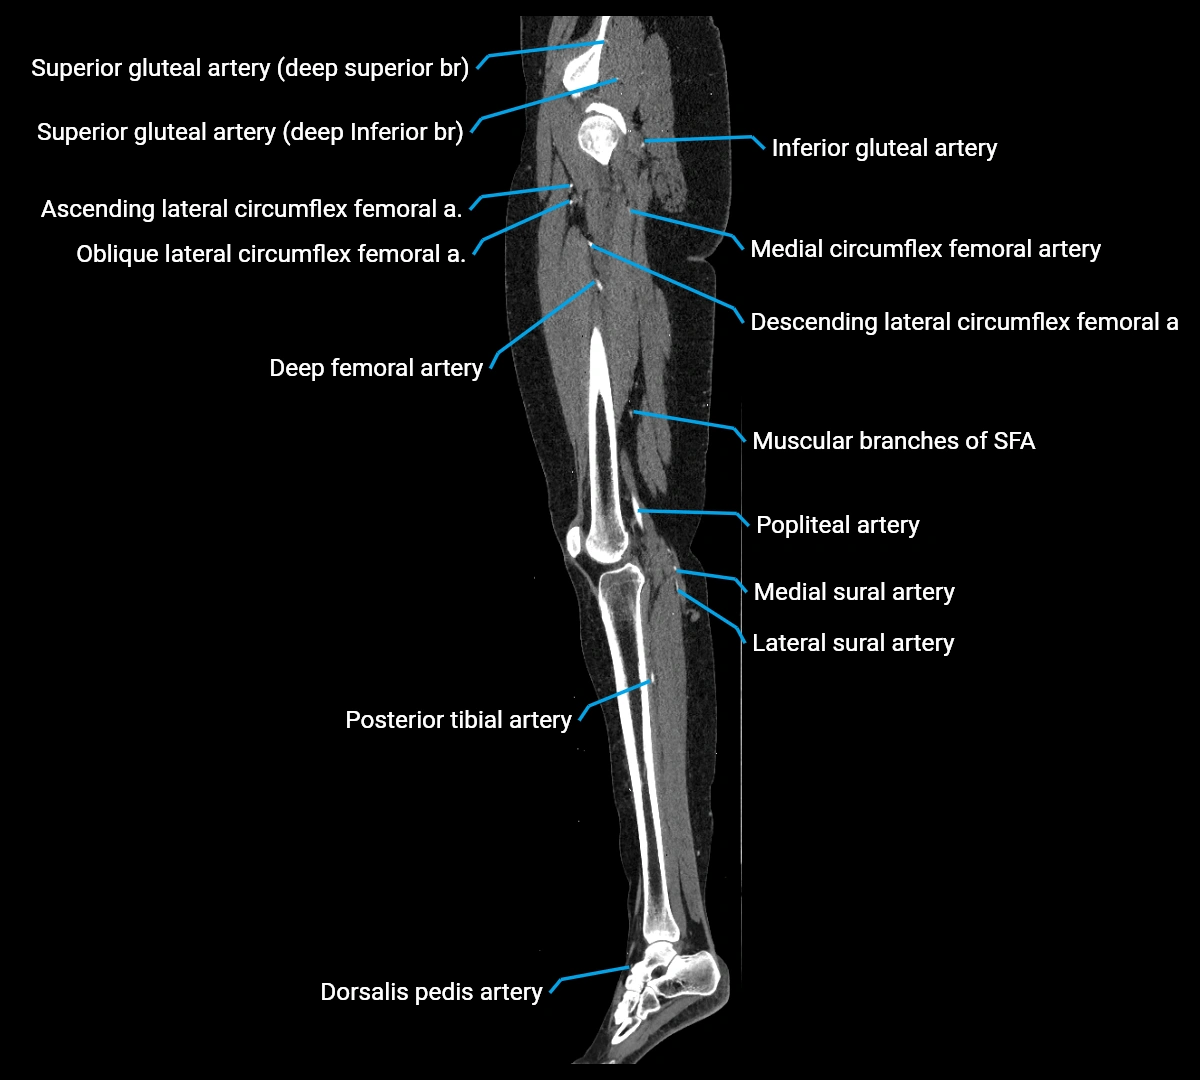

CT images

image

Contrast-enhanced CT (CTA):

• Gold standard for abdominal aortic imaging

• Provides excellent detail of lumen, wall, aneurysm, thrombus, and branch vessels

• Multiplanar and 3D reconstructions help in aneurysm measurement, stent graft planning, and dissection evaluation